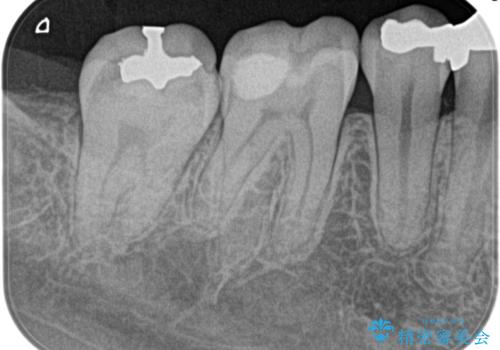

奥歯が痛い。精密根管治療〜オールセラミッククラウン

奥歯の根管治療~オールセラミッククラウン